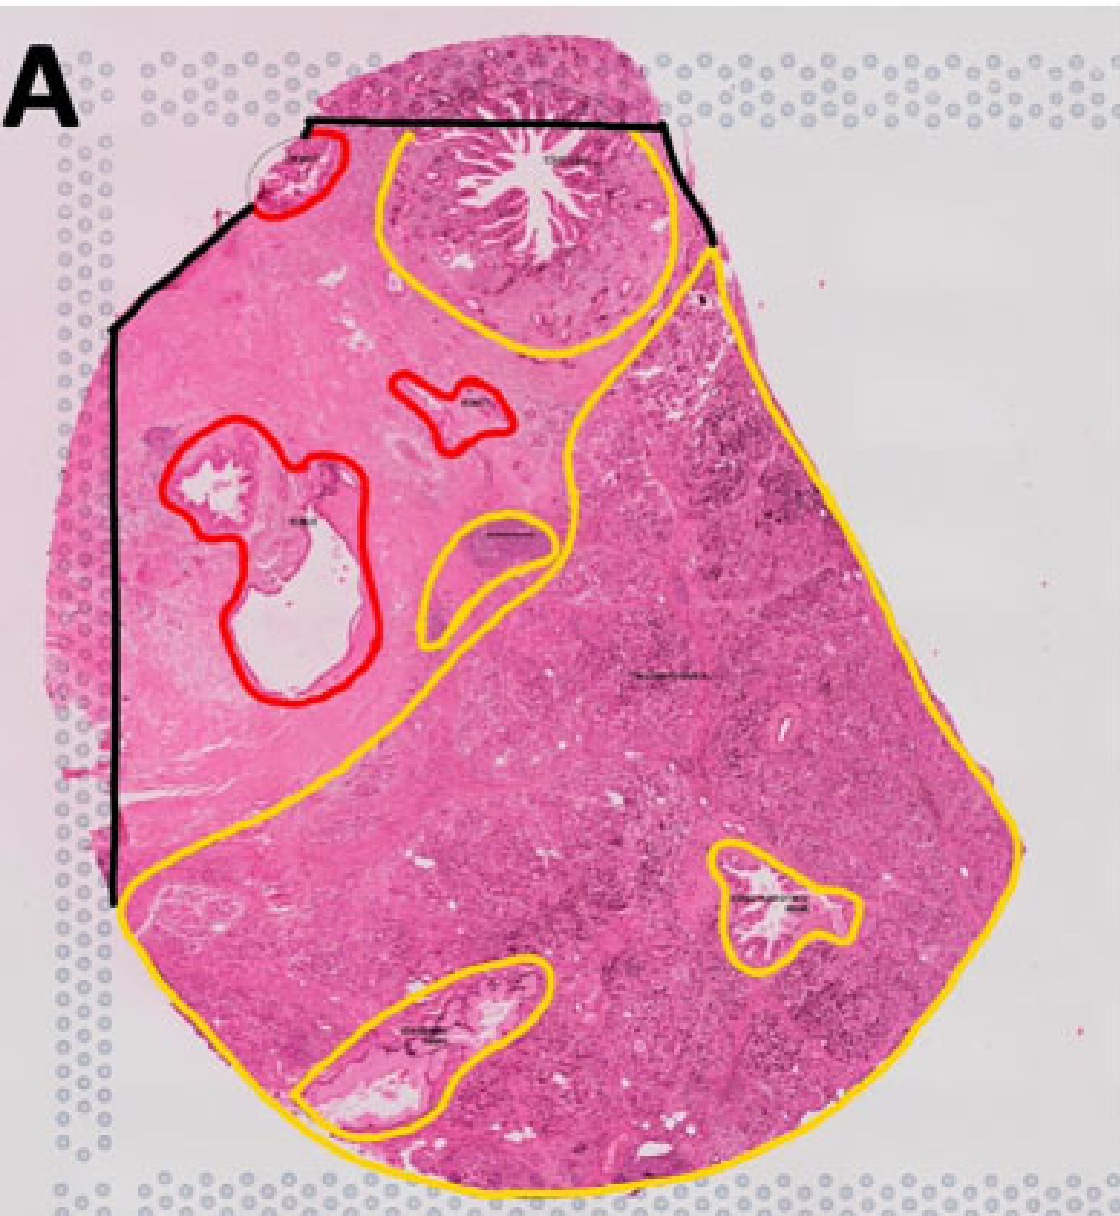

Wei R. et al. - 2022

Spatial charting of single-cell transcriptomes in tissues

Condition Dimension

N/A

Data Components

Biological Annotation

Data

Metadata

None

Modality

Sequencing-based

Resolution of observation

Functional tissue unit

Visualized Elements

Observation

Biological

Tissue

Abstraction

None

Chart Type

Histological image

Communicative/Contextualization

Annotation

Comparative Design

None

Layout

Spatial : Physical

Scalability Strategy

None (Item-level)

Where are tumor regions located within the spatial architecture of a tissue section?